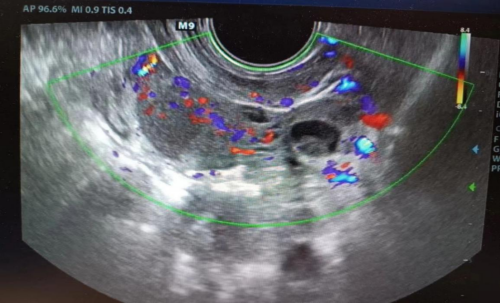

)就诊,入院时由于腹痛剧烈,小雨已经无法正常行走。完善经直肠盆腔彩超后,提其左侧输卵管积液,左侧附件区类“漩涡”样回声,疑输卵管发生扭转,小雨马上被收入妇科住院。

接诊医生廖年春与患儿家长积极沟通并取得其同意后,第一时间为小雨行全麻下“腹腔镜探查术”。术中发现左侧输卵管积液、增粗,直径约5cm,扭转5圈,相当于扭转了1800°,其远端呈暗红色缺血缺氧表现,幸亏入院及时,不然有可能发生输卵管缺血坏死!手术医生将扭转的左侧输卵管进行复位,恢复正常血运,并对输卵管进行修复,完好地保留住了附件。术后,小雨没再出现腹痛的情况,3天后痊愈出院。